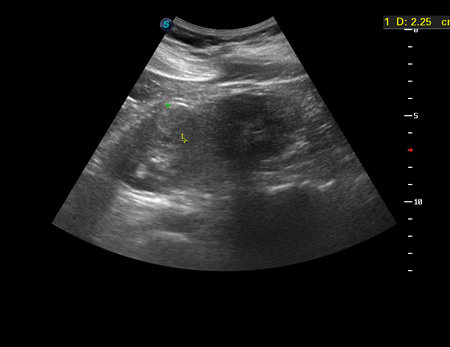

УЗИ, рак почки, малая опухоль. RCC, small tumor, ultrasonography.

Женщина средних лет, жалоб не предъявляет.

Левая почка.

nov272015085251_4.jpg